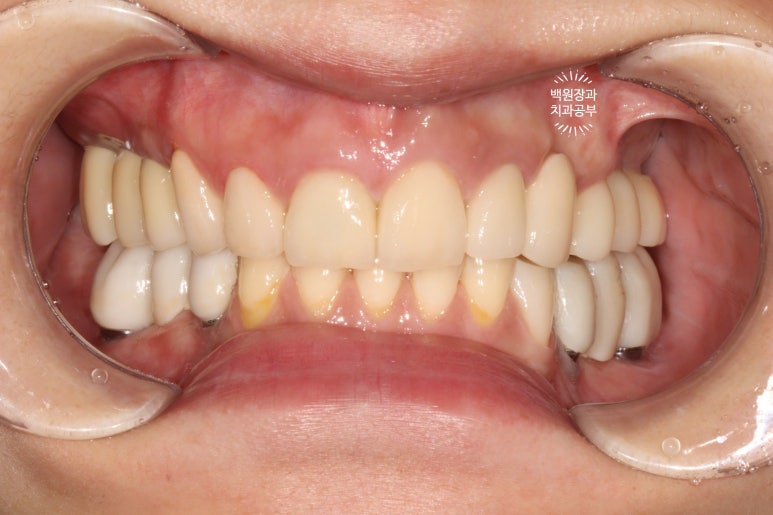

처음에 계획했던 5개의 어금니 임플란트와 3개짜리 지르코니아 브릿지 완성 후 정면 사진입니다.

아주 깔끔하게.... 정말 이상적으로 완성된 것을 보실 수 있습니다.

양 옆모습을 돌려서 보시면 위어금니와 아래어금니가 확연히 비교되는 것을 보실 수 있을겁니다.

일단 치아 경계 잇몸에 은색으로 보이는 부분 없이 깔끔하게 마무리가 되었습니다.

색상도 무조건 하얗지만은 않아서 개인적으로 더 자연스러워졌다고 봅니다.

교합면에서 촬영한 것을 보면, 다수의 치야가 완성되어 드뎌 원래 치아가 있었던 상태로 돌아간 것을 보실 수 있어요.